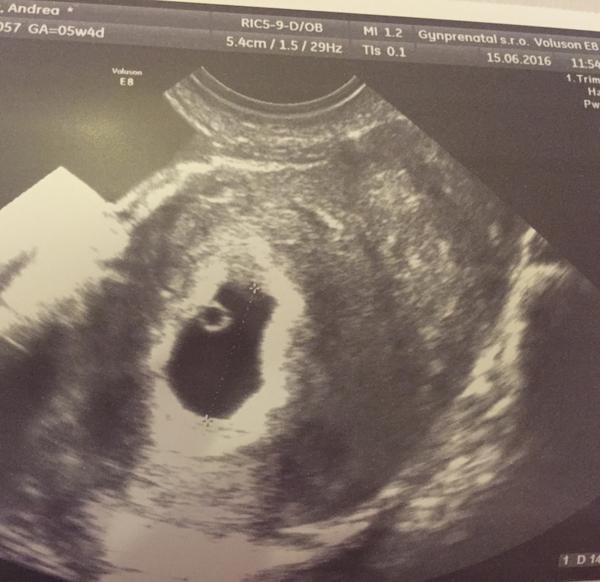

@luciadobrov dakujem 😊 Bublinka ma 7mm a cakame len jedno, som isla s malou dusickou ci nie su dve. 😄